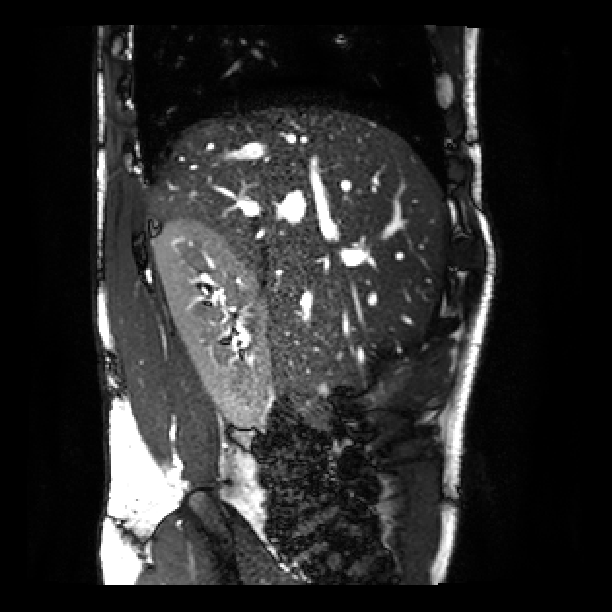

Fig. 3 shows a similar comparison for abdominal MRI of a pregnant patient. As highlighted in the red box, where the artifact is caused by a deep breath, due to lack of a good target with only one stack of 2D MR images, the state-of-art SVR method failed in the area with large motion corruption.

![]() |

| (a) | (b) | (c) |